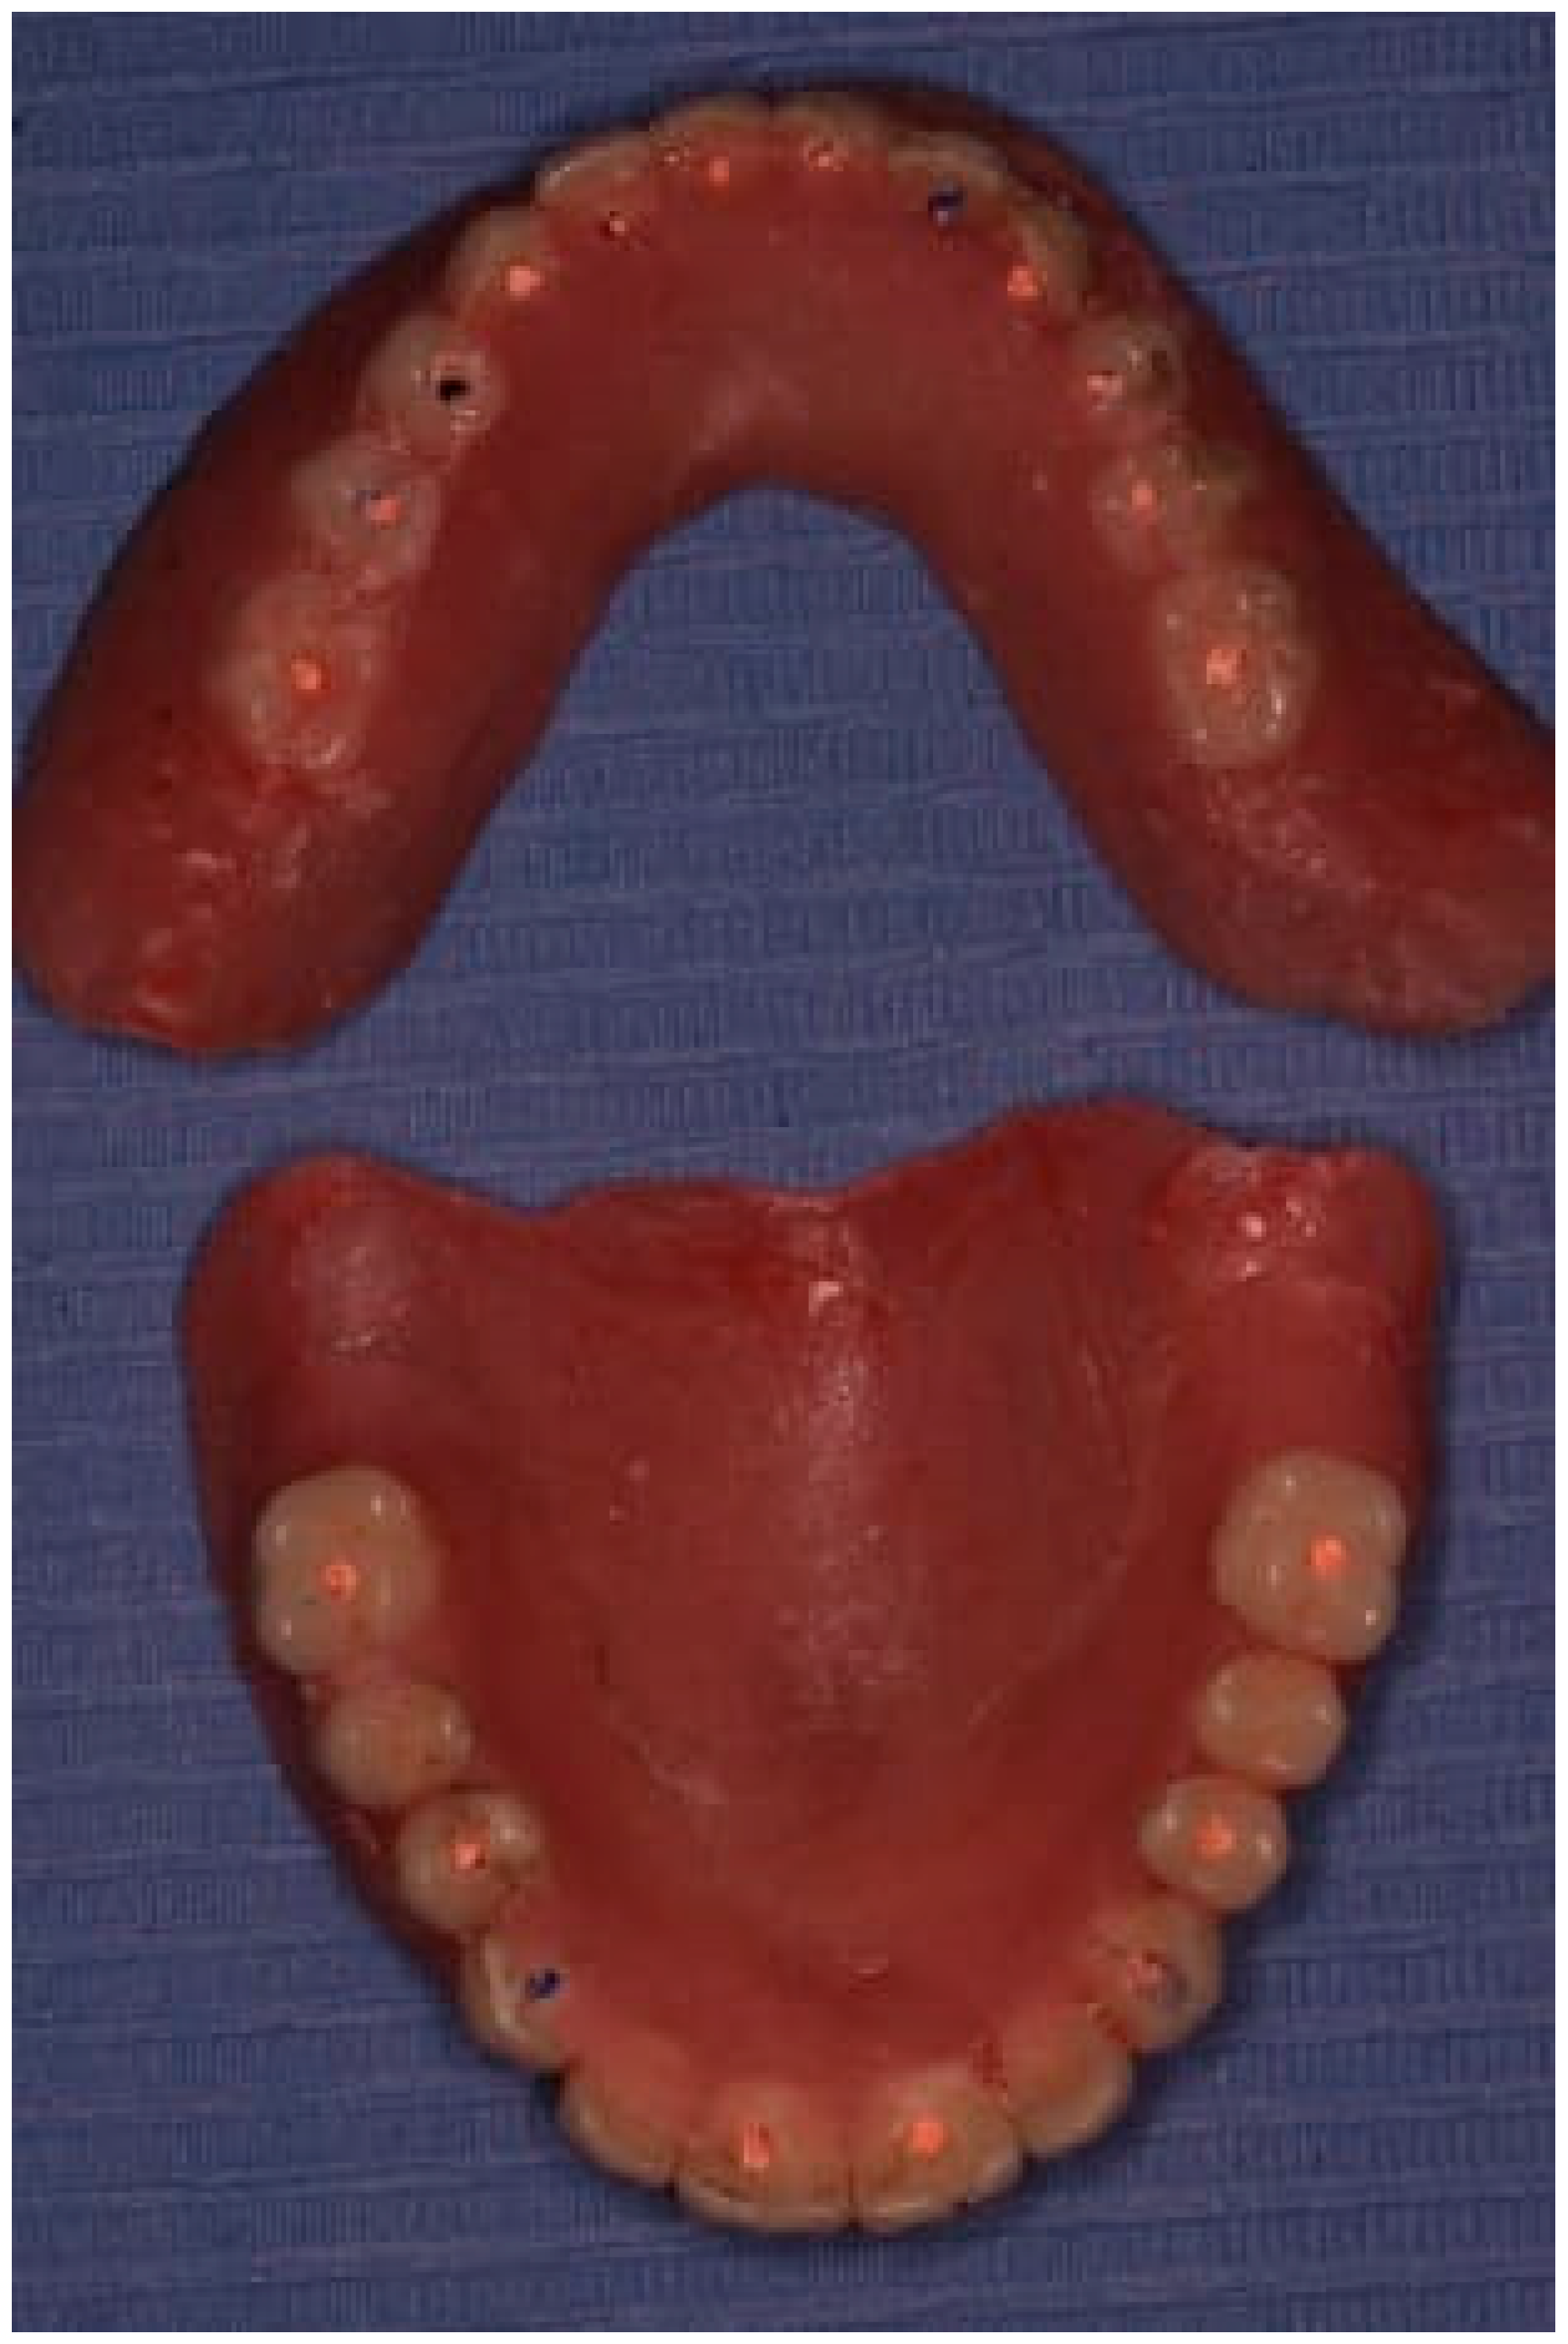

Figure 14. The final prostheses.

The restoration plan involved placing a bridge that connects the central incisors to the canines, along with an additional bridge spanning the first premolar to the first molar on each side of the maxillary arch. In the mandibular arch, the plan included three bridges: one connecting the lateral incisors bilaterally and another bridging the canines to the second premolars and first molars on each side (Figure 14 and Figure 15). Placing was confirmed using Panoramic radiographs obtained using the PantOs DG XP panoramic dental X-ray system (Fona S.r.l., Assago, Italy; CE 0051). The unit operates on a 230 V, 50/60 Hz input line with an 8 A fuse. Standard panoramic exposure parameters were applied (90 kVp, 10 mA, exposure time 14 s) following the manufacturer’s safety recommendations. A trained radiology technician performed all scans, and patient positioning was standardized using the built-in cephalostat support and light-beam alignment to ensure reproducibility of serial images.